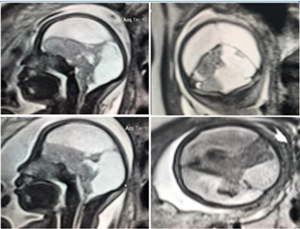

Giá trị của siêu âm trong 3 tháng đầu chẩn đoán nhau xâm lấn bất thường ở thai phụ nguy cơ cao có nhau tiền đạo